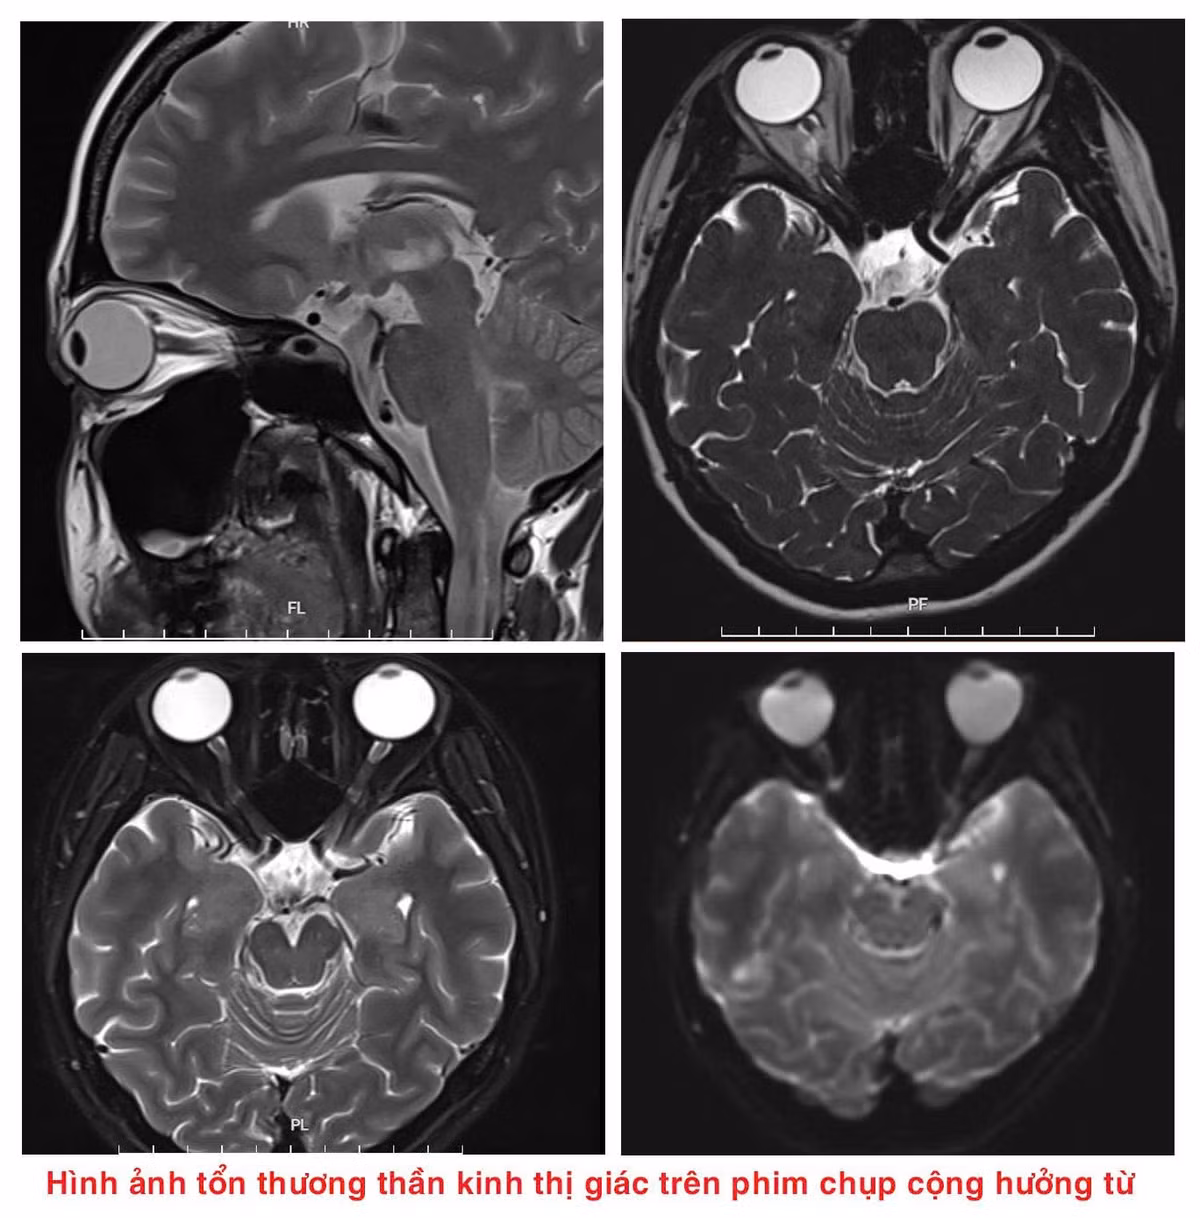

Tại đây, người bệnh được các bác sĩ thăm khám, làm xét nghiệm máu, chọc dịch não tuỷ, chụp cộng hưởng từ sọ não,… Sau hội chẩn lâm sàng, người bệnh được kết luận bị rối loạn Phổ viêm tuỷ thị thần kinh thể tổn thương thần kinh thị, sàn não thất IV, hành tuỷ lưng bên.